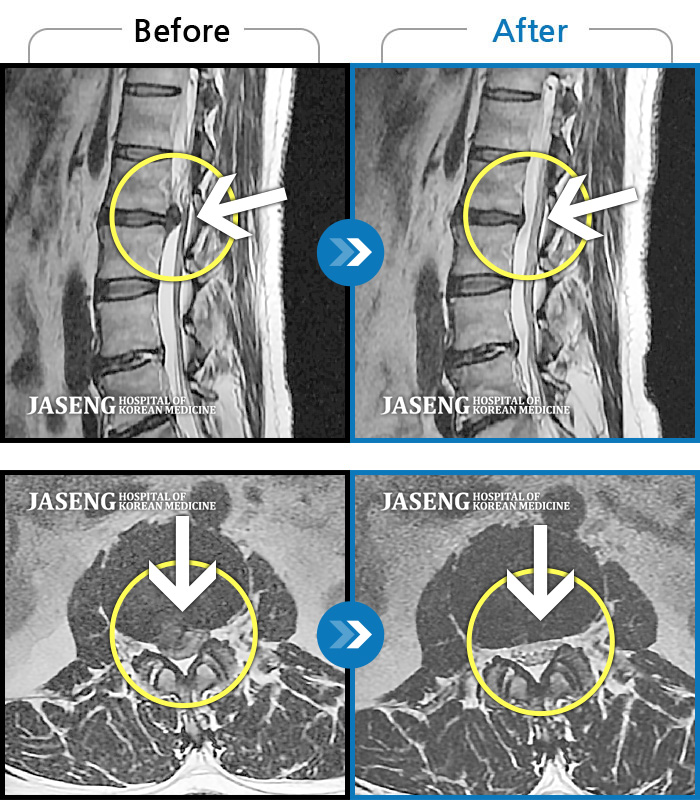

60건의 MRI 전후 사진으로 터진 디스크 흡수 사례를 확인하세요.

※ 환자분에게 사전 동의를 받아 동일 조건에서 촬영되었으며, 개인에 따라 치료 후 부작용이 발생할 수도 있으니 사전에 의료진과 상담 후 치료를 진행하시기 바랍니다.